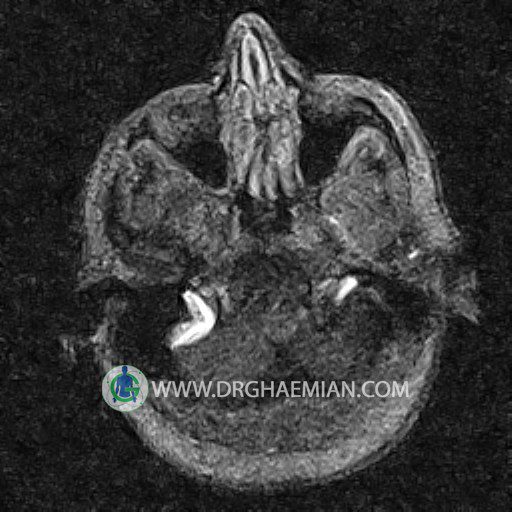

ام آر وی یک روش تصویربرداری دقیق و غیر تهاجمی است که برای معاینه ورید های بدن و ارزیابی سلامت رگ ها استفاده می شود. ورید ها خون را از اعضای بدن به قلب باز می گرداند تا دوباره اکسیژن و مواد مغذی به خون داده شود. ام آر وی جریان خون را ارزیابی و موارد غیرعادی مضر مانند لخته های خونی را شناسایی می کند. در این کیس ترومبوز دیواری مغز در سینوس عرضی راست و ترمبوز جزئی در سینوس عرضی چپ دیده می شود.

Images of the venous cranial vessels demonstrates a superior sagittal sinus of normal caliber with normal arrangement of draining superficial cerebral veins.

The great cerebral vein Galen inferior sagittal , straight sinus and left sigmoid sinus appear normal.

The right sigmoid sinus present a normal caliber.

– Narrowing of left transverse sinus with filling defect & inthimal irregularity

suggestive for partial thrombosis

– Inthimal irregularity in anterior wall of right transverse sinus suggestive for mural thrombosis

are seen